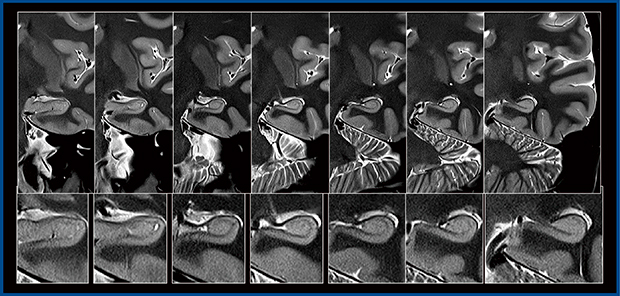

記憶ネットワークは非常に複雑だが,主に視床と海馬から成り立っている。最近,多発性硬化症のマウスモデルにおいて,記憶障害がきわめて初期の段階で発症することを報告した1)。これはヒトも同様であり,記憶障害の原因は海馬の変化によるもので,なかでも歯状回はほかの部分よりも多発性硬化症の炎症に対して脆弱なことがわかってきた。そこで,従来のMRI装置のT1コントラストを用いてヒトの海馬の解剖学的構造について研究しているが,歯状回とCA4(歯状回門に相当)を分離して描出するのは困難である。海馬の解剖学的構造は非常に複雑で,さまざまな層や領域から成り立っているが,超高磁場 7T MRIを用いることで観察可能となった。一方,次世代3T MRI Galan ZGOでは,新しい技術との組み合わせにより,7T MRIと同等の画像を得られる可能性が出てきている。

また,多発性硬化症による海馬への影響を解明して認知機能の向上を図ることに加え,拡散テンソルなどの先進的な技術を用いて,さらにその先の先進的な研究を進めていくべきであると考えている。拡散テンソル画像(DTI)では,コントロールマウスにおける歯状回の特定の領域の樹状突起や神経を描出でき,多発性硬化症の初期の神経傷害の様子を確認できる。樹状突起が減少すると,水の拡散の制約がなくなり方向性が失われていくが,高分解能DTIを用いることで,きわめて初期の段階における海馬の変化をとらえることができる1)。

また,傾斜磁場性能の向上がもたらすもう一つの利点は,真の拡散現象を検証していけることである。b値を大幅に上げると拡散による信号欠損が増加していく。われわれは,標準的なb値で撮像すると微細な構造が不明瞭となるが,b値が高くなると変化に非常に鋭敏になるため,微細な構造描出が明瞭となることを報告している2)。マウスでの実験でこの変化を観察すると,標準的なb値では特定できないが,b値を変化させることで特定できることが判明している。例えば,b値を500から5000まで変化させた拡散強調画像では,b値の上昇に伴い感度が向上し,微細な構造が明瞭化している。海馬の神経細胞が交差している部分をさまざまな方向から等方性で計測すれば,海馬構造の高精度な特定につながると考えている。